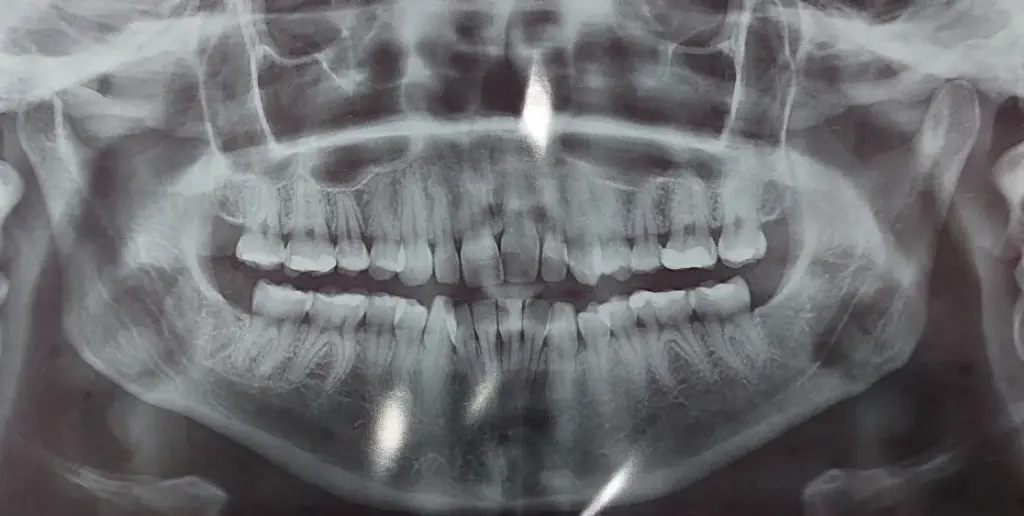

До редакції «Кременчуцького Телеграфа» звернулася місцева жителька Сніжана. Вона упродовж кількох років користувалася послугами приватної стоматологічної клініки «Міла-Дент», що знаходиться у Кременчуці за адресою вул. Винахідниці Ющенко, 15/1. У 2023 році нашій героїні там вирвали зуби мудрості та пролікували кілька інших зубів. Робили це на той час різні лікарі — і в пацієнтки ніяких претензій не було. Але після цього їй порадили вставити брекети — дівчина погодилася.

У квітні 2025 року брекет-систему Сніжані встановили на верхню щелепу, а за місяць почали займатися нижньою. Саме тут і почалися проблеми.

Із нижньої щелепи у дівчини постійно вилітала дуга та відпадали брекети. А так бути не повинно. Тому вона знову звернулася до лікарки Василенко. Наприкінці липня дівчині вирвали два зуби — нижні 4-ки. Стоматологиня сказала, що це має вирішити ситуацію. Крім того, після видалення зубів жінка почала стягувати брекетами інші зуби, аби закрити простір, що утворився на місці видалених.

Проте брекети продовжили відпадати й далі. У вересні на прийомі стоматологиня припустила, що причиною цьому може бути суглоб або щелепна кістка, що заважають зубам рухатися. У листопаді лікарка призначила дівчині одягати на ніч еластики, аби ті швидше стягнули зуби.

Видалення можна було уникнути

— Лікар також сказав, що у моєму випадку не було ніякої необхідності виривати нижні 4-ки. І при цьому лікарка неправильно потягнула зуби еластиками, тому так і сталося.